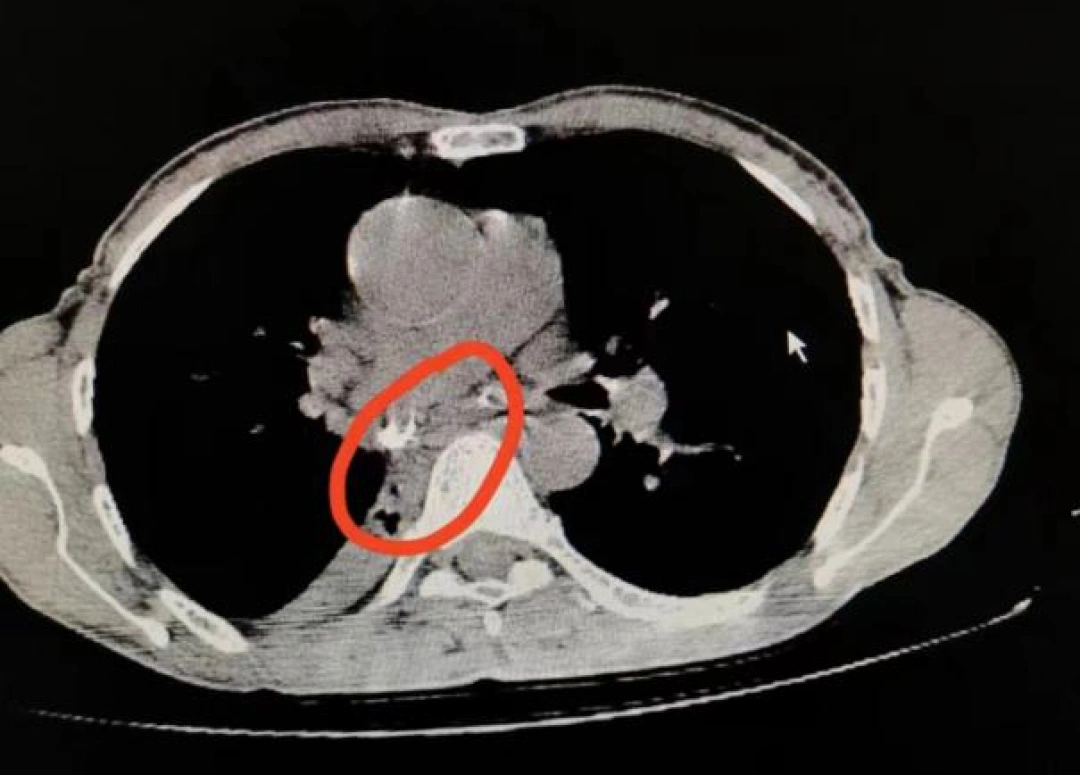

在湖南省第二人民医院呼吸与危重症医学科曾祥伯主任带领的团队系统的诊治下,发现患者肺部有大面积肺不张,严重感染,并且形成了肺脓肿。结合临床症状,再次CT的检查后,曾祥伯主任考虑为气道异物局部炎性肉芽肿形成引起的,支气管阻塞可能性大,肺癌的可能性较小。

△入院时CT影像

气道异物非常危险,如果气道内出现了“不速之客”,长时间在异物的刺激下,呼吸道分泌物增加或堵塞物膨胀,可导致反复咳嗽、咯血、咳脓痰、高热等症状,这些症状与肺癌的症状非常相似,而且异物会慢慢被肉芽包裹,在CT检查的影像下,很容易被诊断是肿瘤。